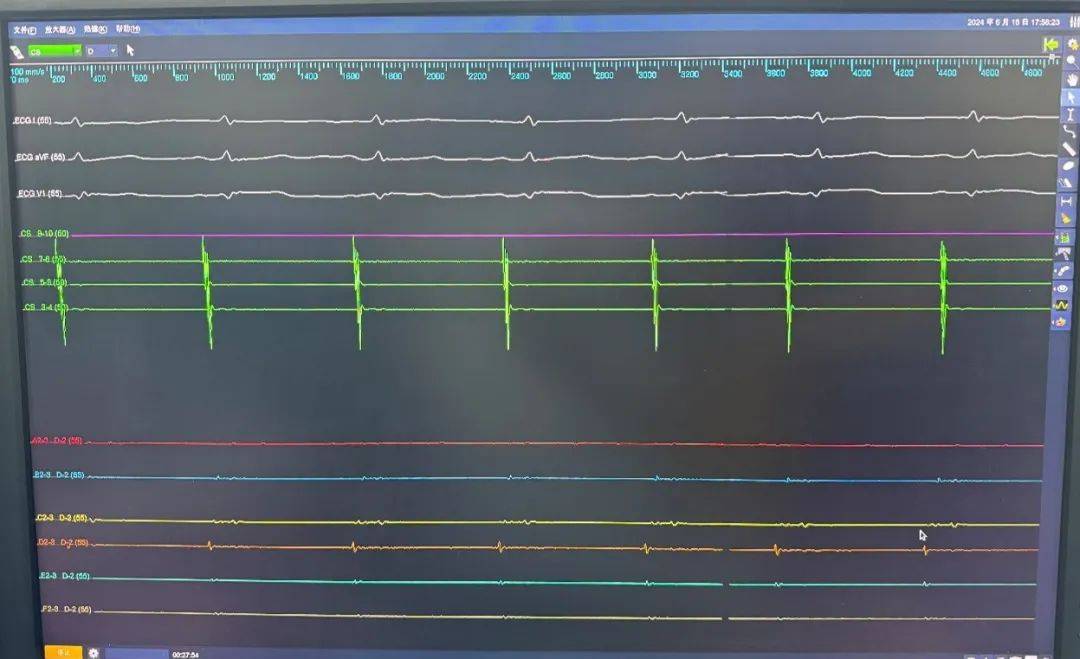

LSPV消融前电位

LSPV消融后电位

LIPV消融前电位

LIPV消融后电位

RSPV消融前电位

RSPV消融后电位

RIPV消融前电位

RIPV消融后电位

TIGNSN Sonic Eyes 10指导下,行房间隔穿刺,脉冲消融导管沿可调弯鞘管进入左房,测量基线阻抗后,依次将脉冲消融导管送入左上肺静脉、左下肺静脉、右上肺静脉、右下肺静脉四个肺静脉口部与前庭实施脉冲电场消融。术中采用脉冲电场消融自身标测电极进行电位标测,消融即刻及消融结束后四根肺静脉电位消失并双向传导阻滞,ICE确认心包正常,结果达到手术预期效果,手术顺利结束。